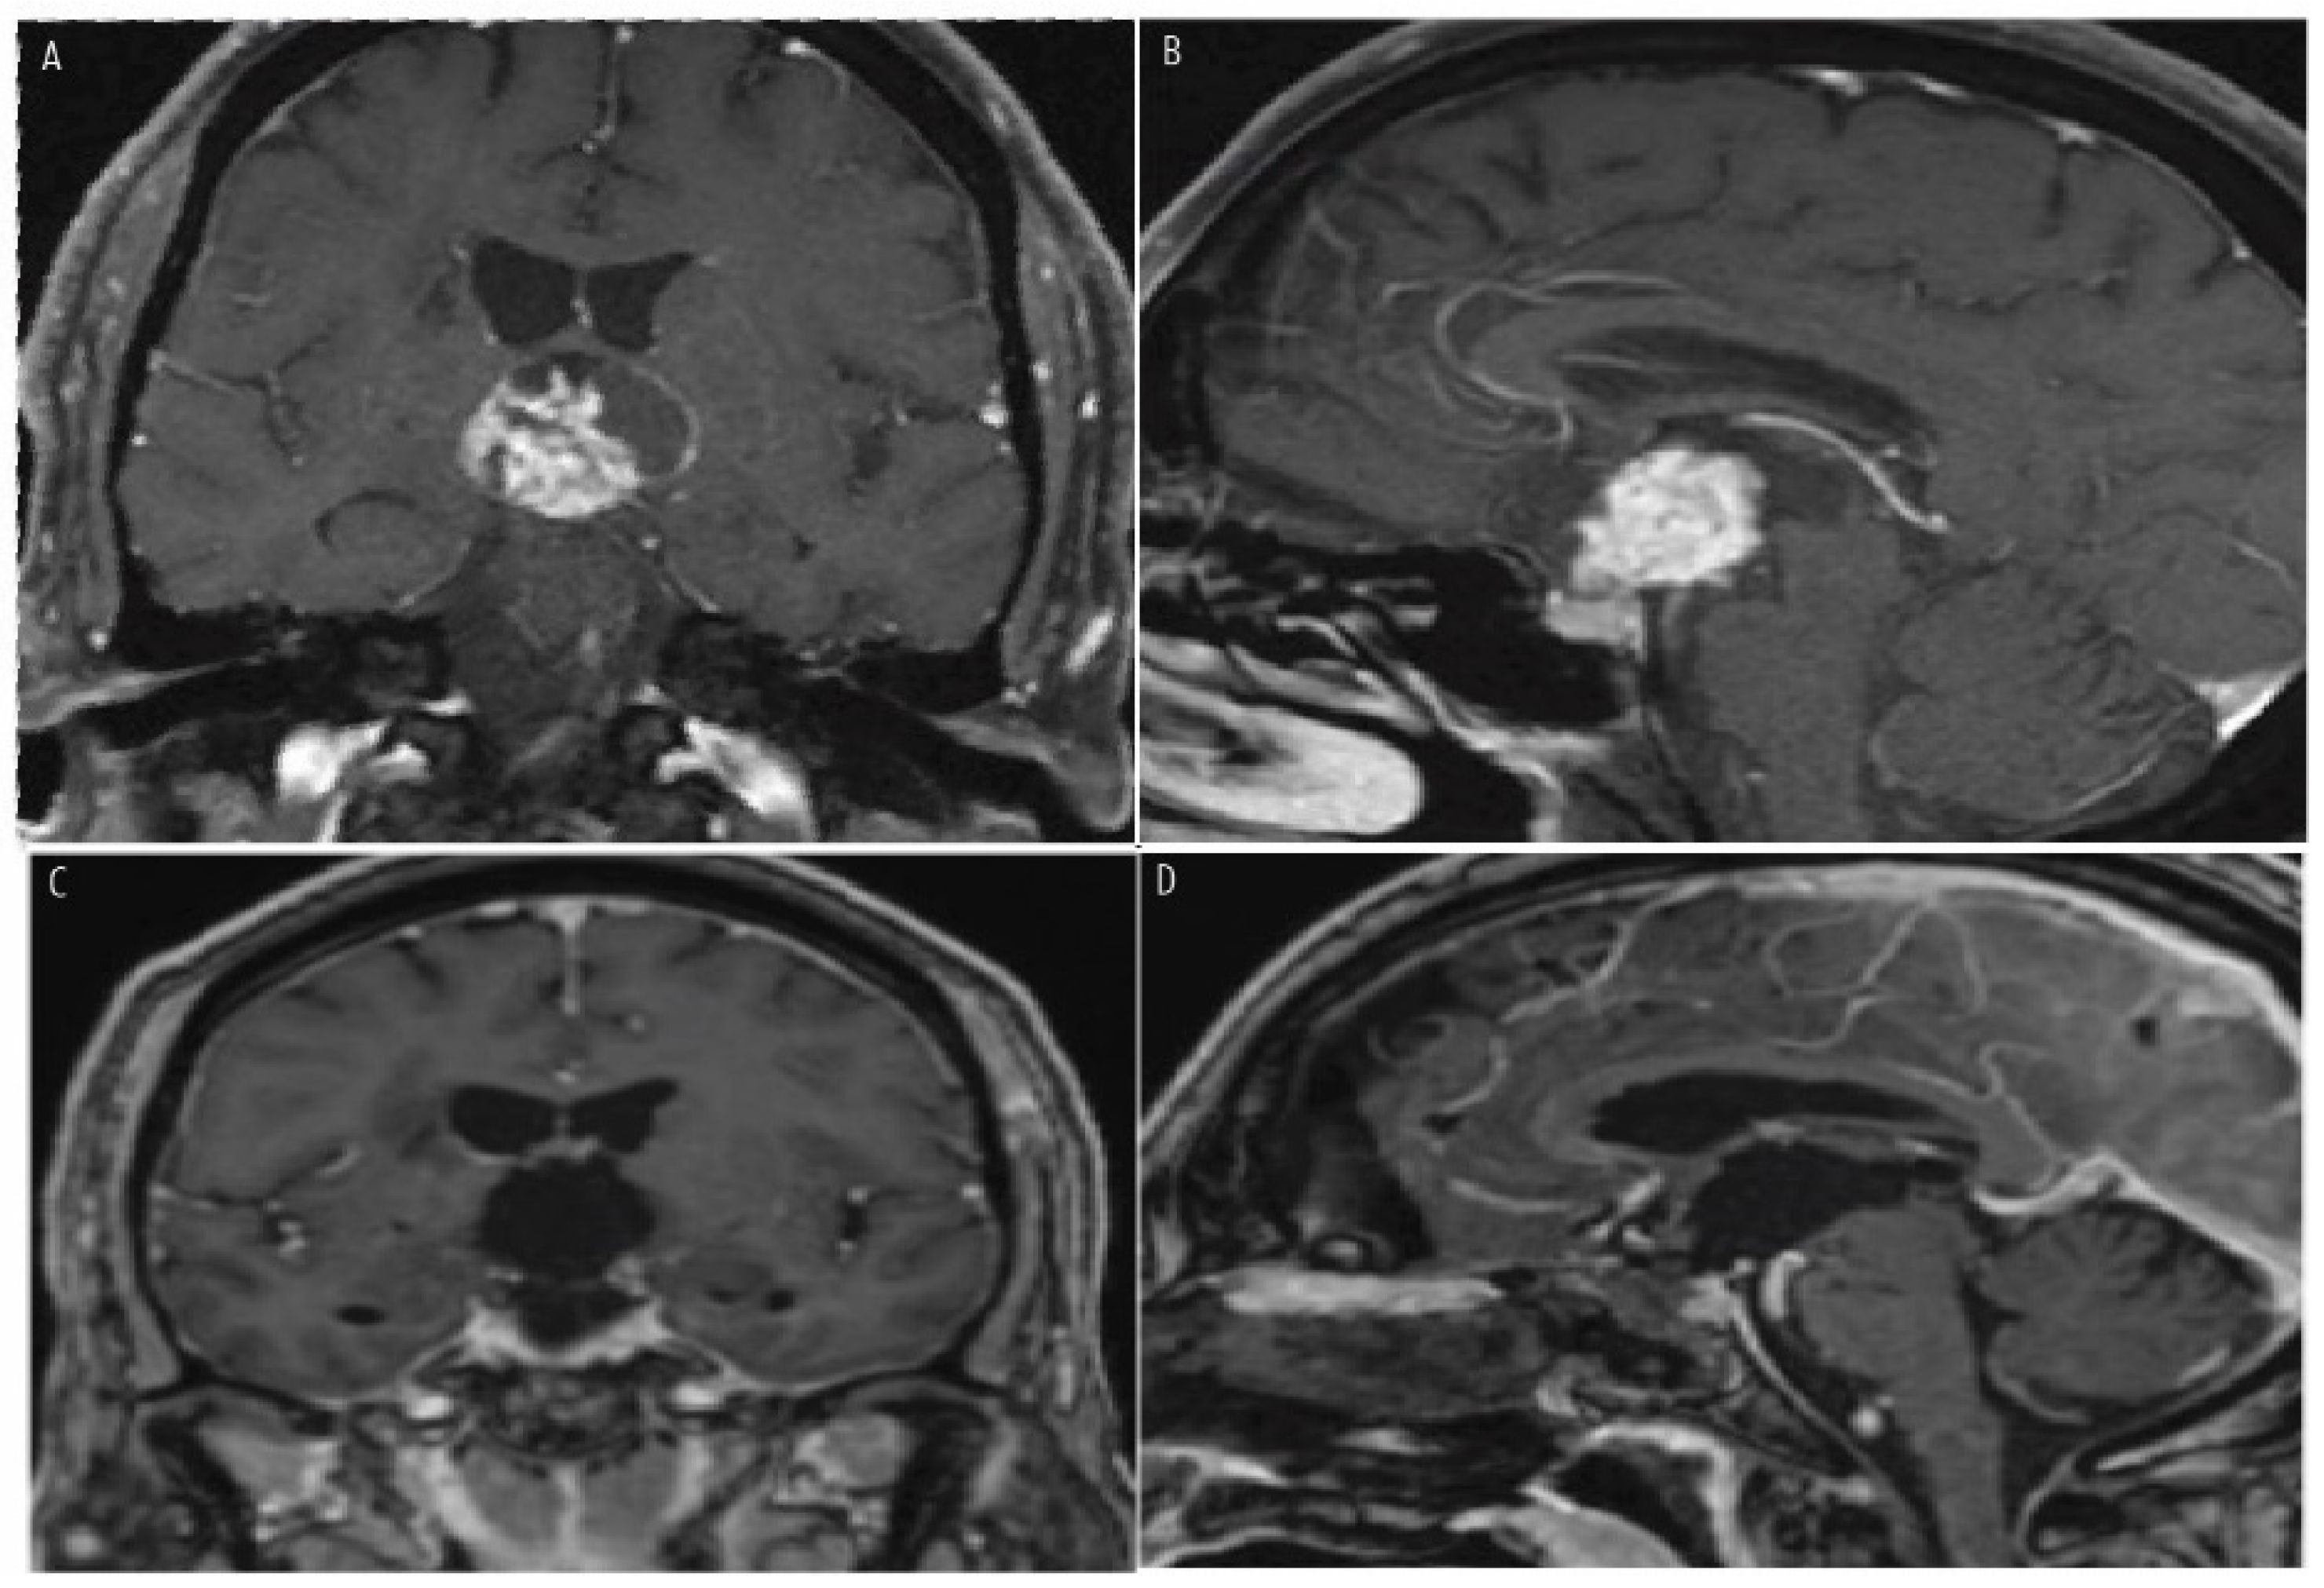

7. Histopathologic Features and Radiologic Features

- Calvanese, F.; Jacquesson, T.; Manet, R.; Vasiljevic, A.; Lasolle, H.; Ducray, F.; Raverot, G.; Jouanneau, E. Neoadjuvant B-RAF and MEK Inhibitor Targeted Therapy for Adult Papillary Craniopharyngiomas: A New Treatment Paradigm. Front. Endocrinol. 2022, 13, 882381. [Google Scholar] [CrossRef]